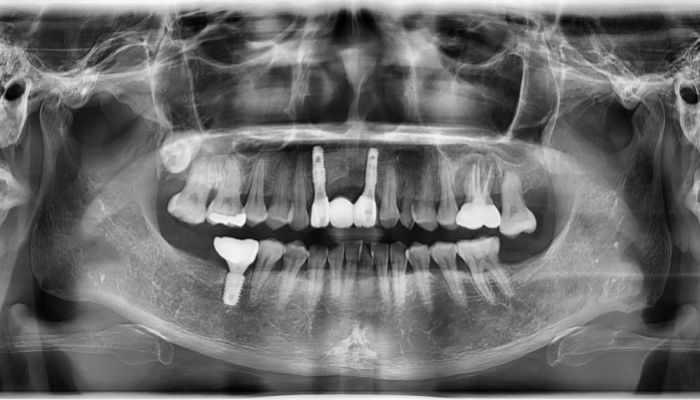

상악동거상술 전후 사례

• 식립 전

식립 후